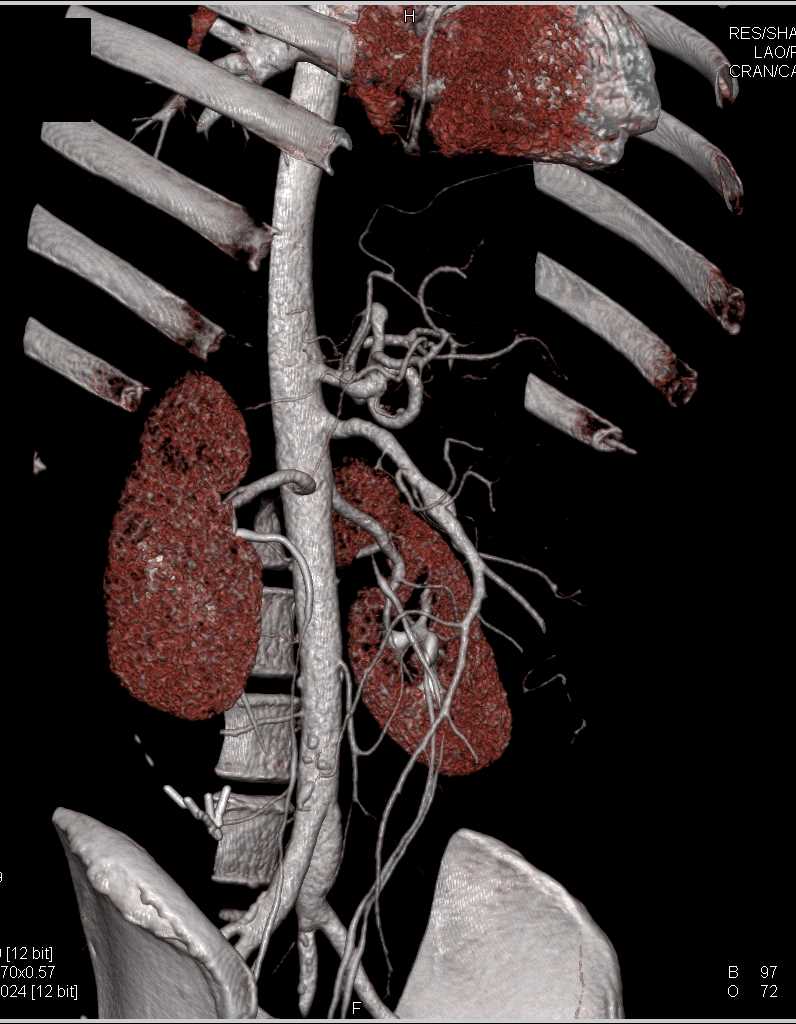

SMA Stenosis